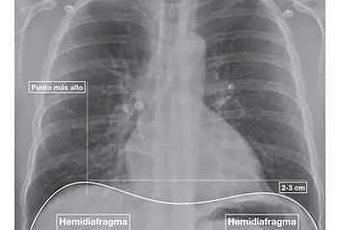

Radiografía de tórax interpretación, correcta valoración de radiografía ap de tórax, anatomía de tórax